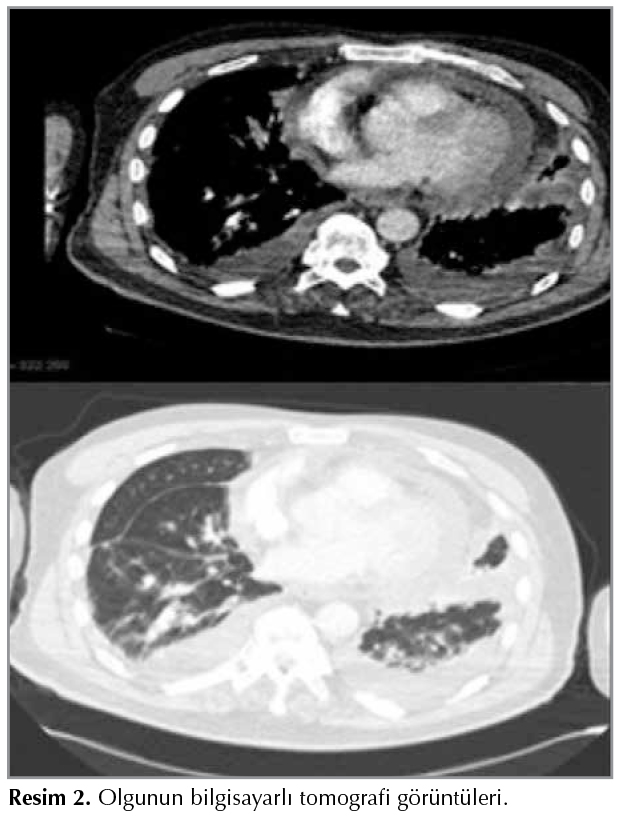

Laboratuvar testlerinde; sedimentasyon 64 mm/saat, CRP: 19 mg/dL, D-dimer 3.42 ?mg/mL; arter kan gazında; pH: 7.48, PaO2: 55 mmHg, PaCO2: 34 mmHg, HCO3: 26 mmol/L, SaO2: %89 idi. Pulmoner emboli protokol?nde toraks tomografisinde; pulmoner emboli saptanmadı perikardda en kalın yerinde 22 mm ulaşan ef?zyon her iki hemitoraksta plevral ef?zyon ve komşu akciğer parankiminde kompresif atelektazi saptandı (Resim 2).

Resim 2